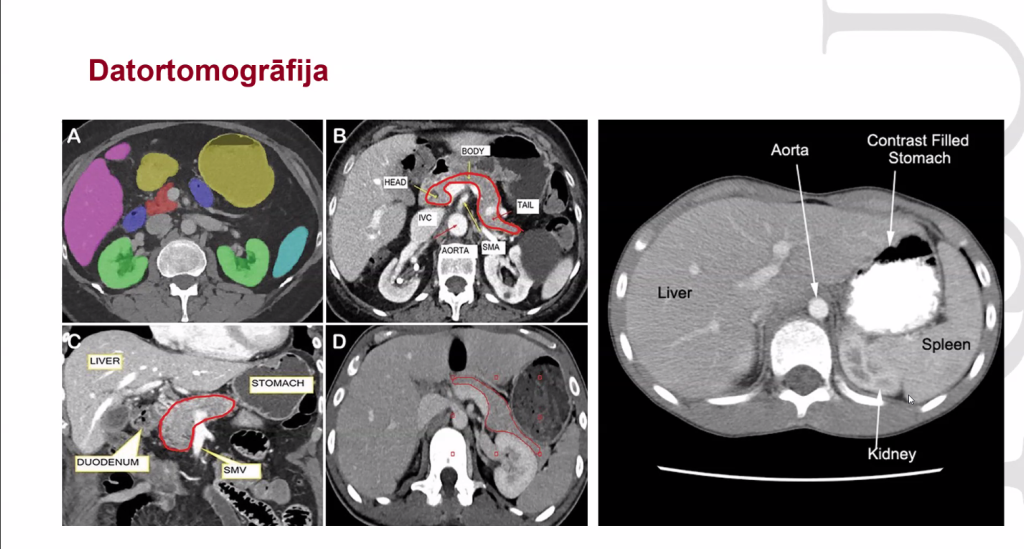

Februāra RSU Jauno Mediķu akadēmijas nodarbība veltīta Radioloģijai, medicīnas nozarei, bez kuras nav iedomājama mūsdienu medicīna, kaut gan vēsturiski radioloģija ir samērā jauna nozare. Savukārt radiologs ir sertificēts ārsts, kurš specializējas diagnostikā. Diagnostikā ir metodes, kurās neizmanto jonizējošo starojumu – ultrasonogrāfija un magnētiskā rezonanse, kā arī metodes, kurās izmanto jonizējošo starojumu – rentgenogrāfija un datortomogrāfija. Neapšaubāmi arī radioloģijā ienāk mākslīgais intelekts. Starp citu, radiologa profesija ir viena no labāk atmaksātajām profesijām Latvijā!